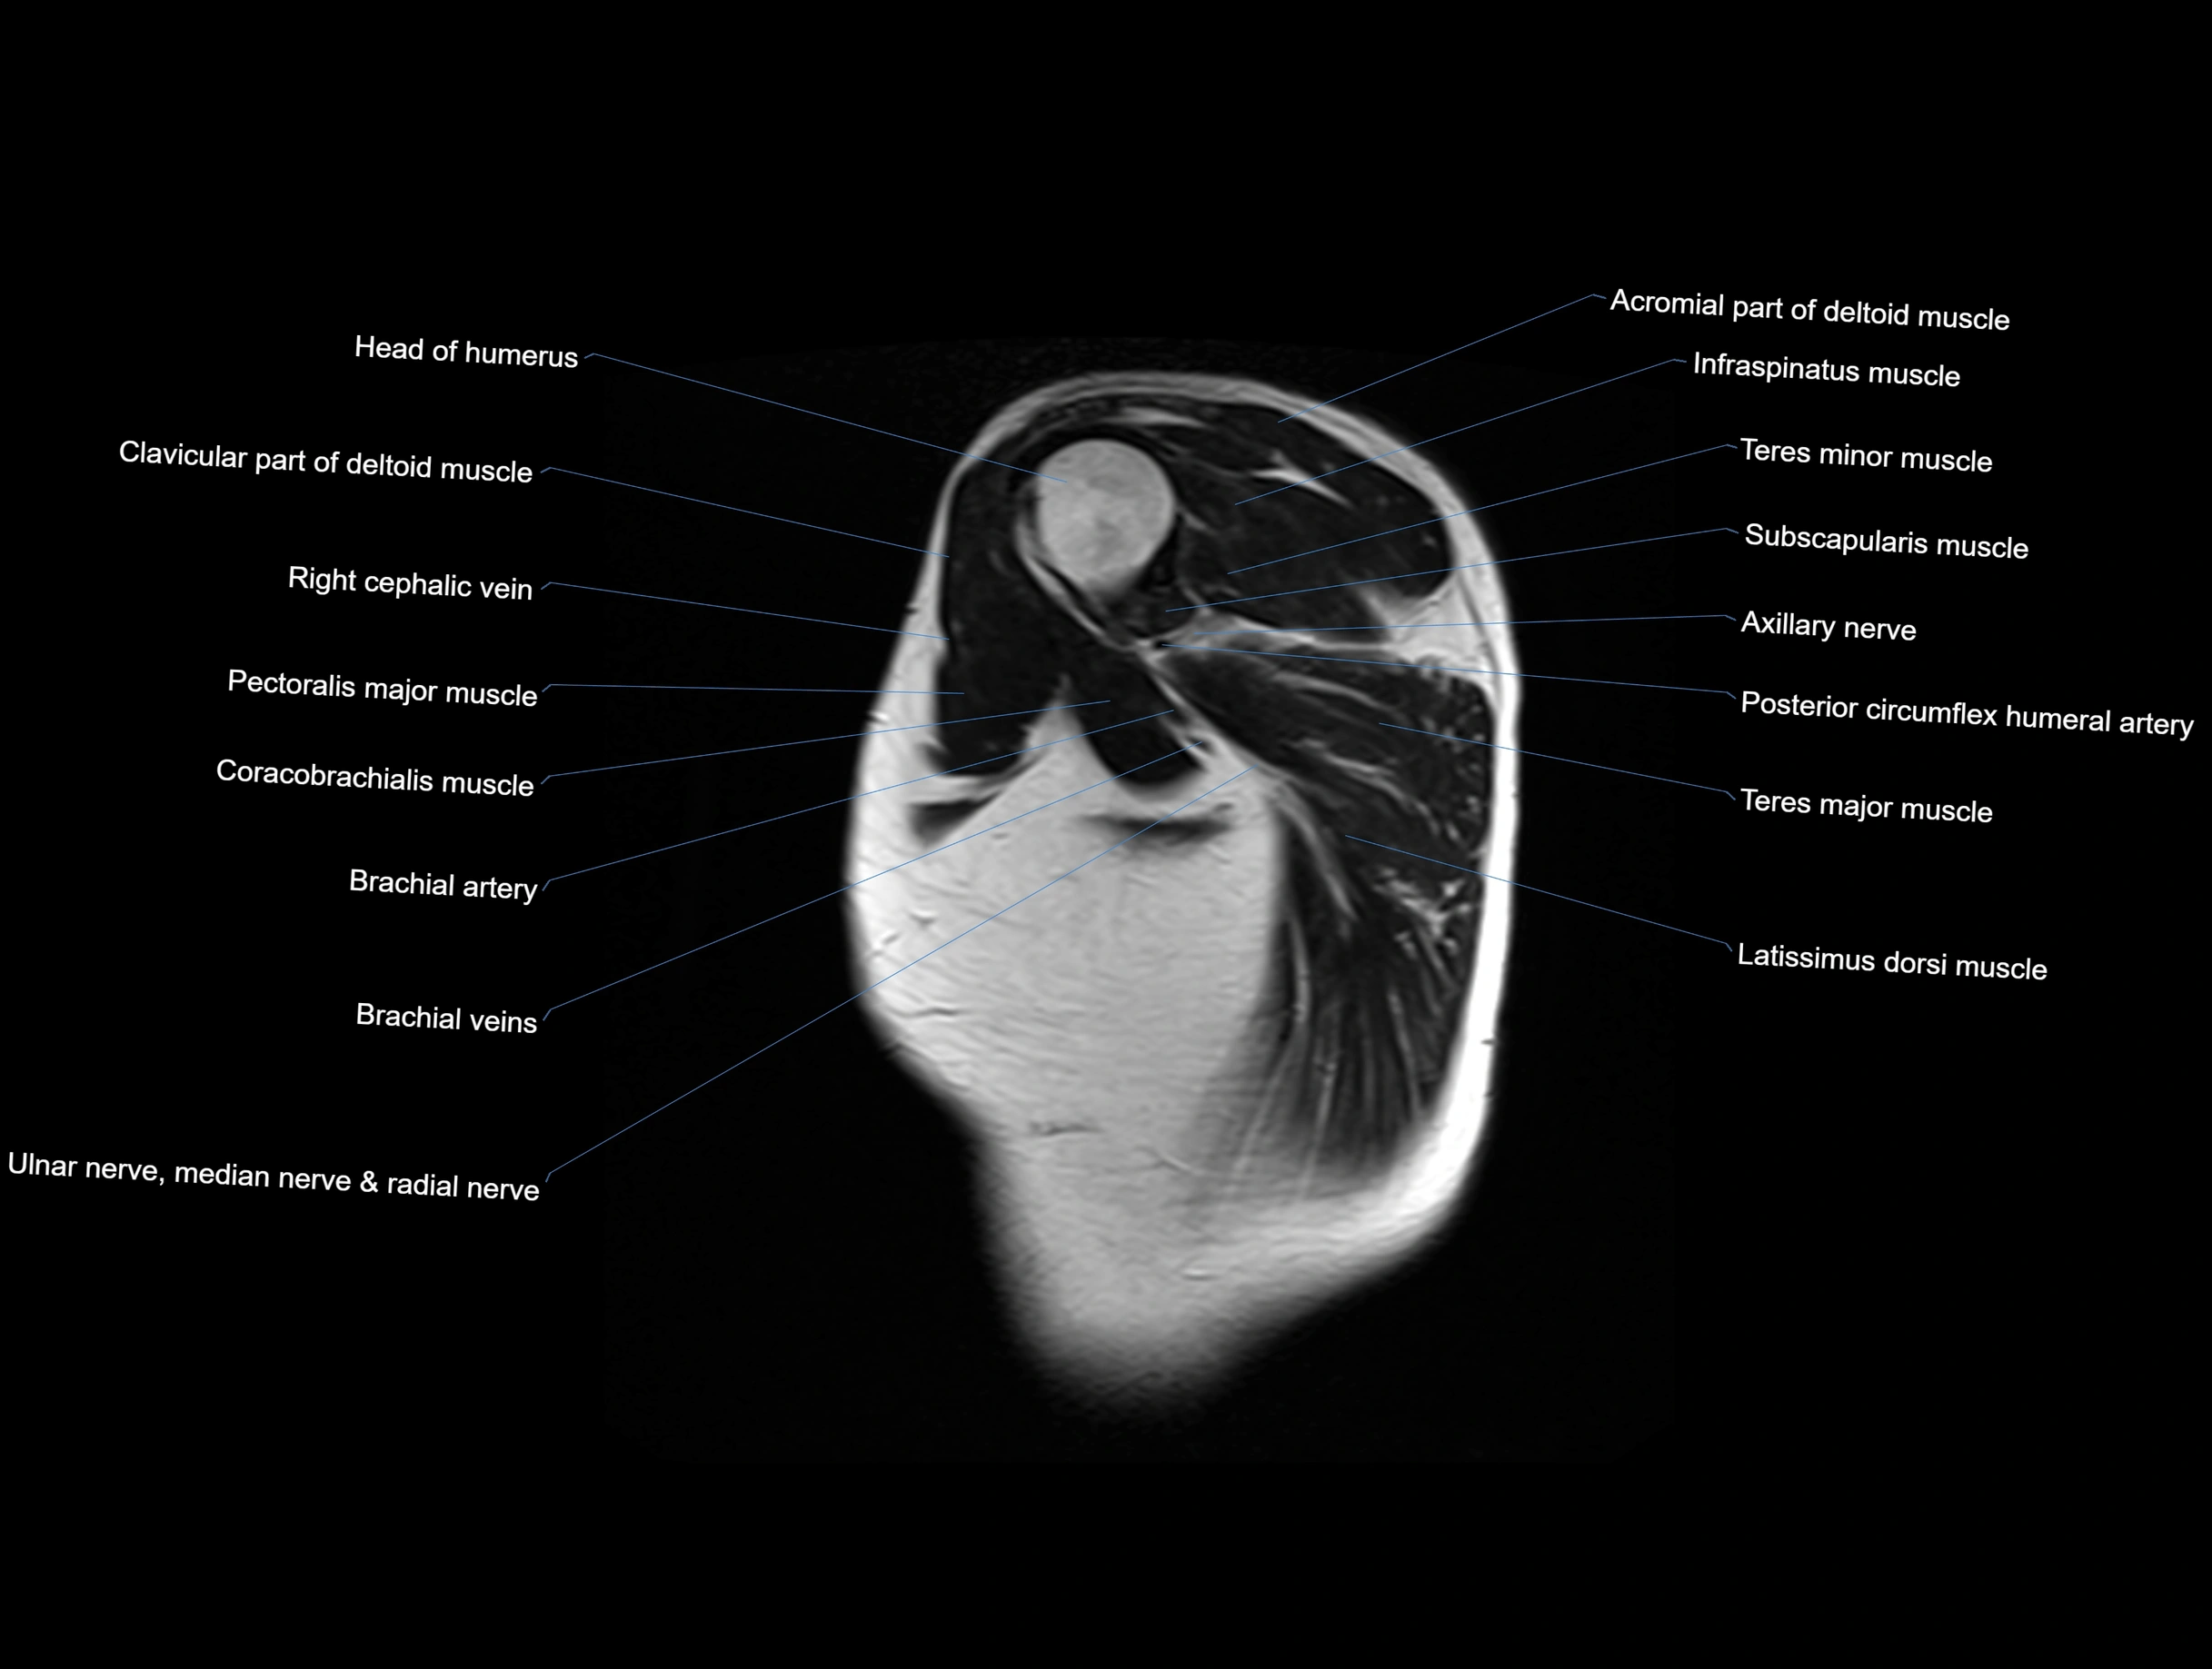

MRI images